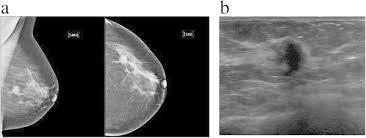

In some people, breast cancer growth can be very slow. Often, there is no lump that can be felt during a physical exam or seen in a screening mammogram.in addition, most women diagnosed with inflammatory breast cancer have dense breast tissue, which makes cancer detection in a screening mammogram more difficult. Major improvements in public health and medical care have resulted in dramatic increases in longevity. After going to my gynecologist with a rash on my breast months prior, i was told. If you're at least 70 years old, your chance of developing breast cancer in the next 20 years is about 1 in 26; Women who've had breast cancer can still get other cancers. Diagnosing breast cancer in women under 40 years old is more difficult, because their breast tissue is generally denser than in older women. When breast cancer is seen in an adolescent, it is frequently caused by spread from another site in the body or from structures within the breast such as tumors of blood vessels. 5% of breast cancer cases occur in women under 40 years of age. Yes, the statistics are far higher in older women, but do you really want to bet your life on the numbers? Younger women generally do not consider themselves to be at risk for breast cancer. Primary breast cancer is rare before age 25 yrs. And it's very hard to pin down how aggressive.